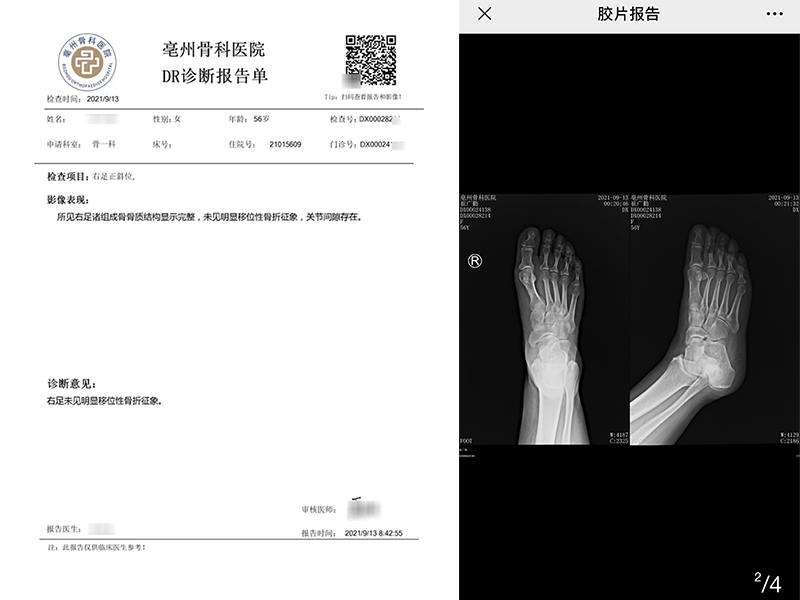

电子报告&电子胶片

原始影像